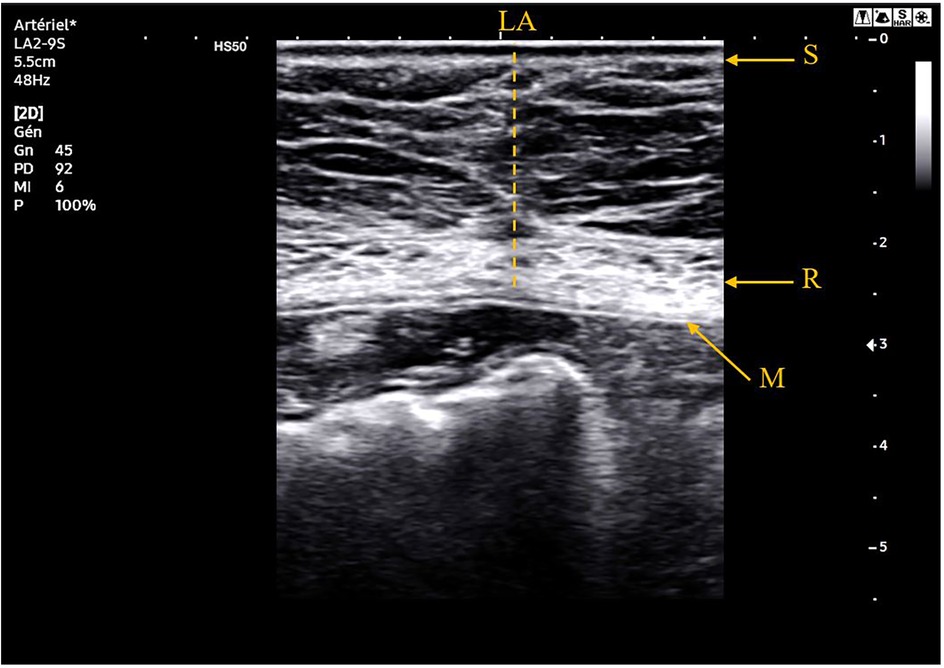

Abdominal ultrasound

The ultrasound was performed using a defined protocol by a Samsung Medison HS50® with a convex probe (CA1-7AD®) for studying the aorta and a linear probe (LA2-9S®) for examining the abdominal wall and visualizing the mesh. The mesh appears as a retromuscular hyperechoic image. A normal ultrasound examination is shown in Figure 1.

Ultrasound image of the abdominal wall in a transverse plane showing normal anatomy.

Figure 1. Ultrasound image at 78 months of follow-up of a 76-year-old patient who did not present any incisional hernia. S, skin; R, rectus abdomini muscle; LA, linea alba; M, retromuscular mesh.